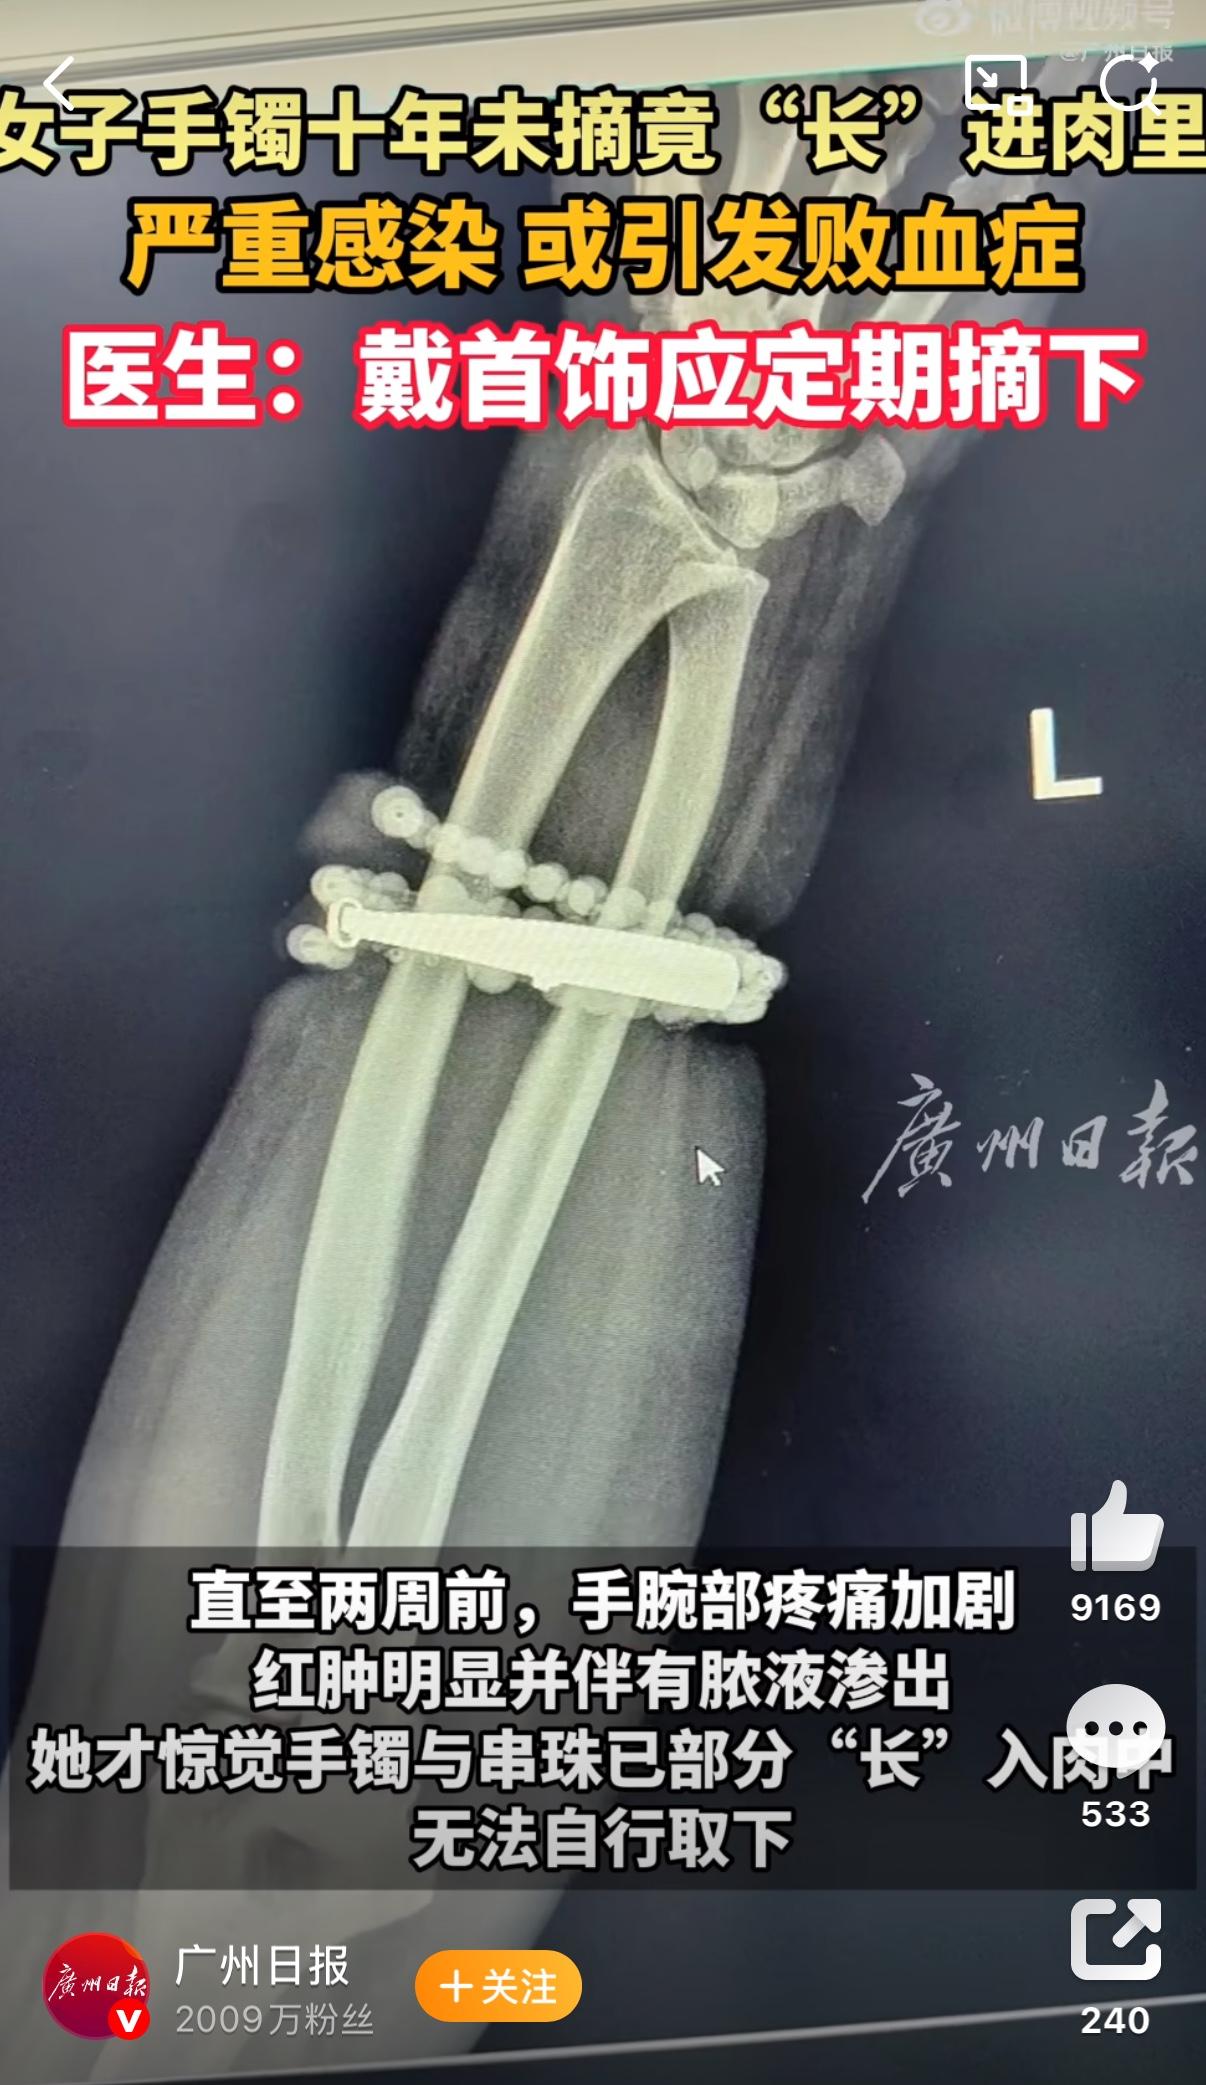

吓出一身冷汗!女子手镯戴10年没摘,竟和肉长在一起差点废了手! 福建一位33岁的女士,十年前戴上婆婆送的银手镯和自己买的玛瑙串珠后就从没摘过,从当初刚结婚90斤的姑娘长到120斤,手腕变粗手镯却越勒越紧,直到半年前皮肤反复发痒发红,她误以为是皮炎随便涂了点药膏,直到两周前手腕红肿流脓,手镯嵌进肉里碰一下都钻心疼,这才慌慌张张去了医院。 医生检查后都吓了一跳,手镯已经和肉芽组织紧紧粘在一起,再不手术不仅手臂功能可能保不住,还可能引发败血症危及生命,最后花了一个多小时才小心翼翼把手镯从肉里剥离出来。 有异常这么久还不去就医,是真能忍啊!不是自己看着视频就觉得疼。平时自己带个手表戒指啥的睡觉钱都会取下来,总是感觉有异物,一直带着更是觉得皮肤“喘不过气”。 其实生活中也一样,很多时候我们明明发现了问题,却因为“麻烦”“习惯了”“没在意”而一拖再拖,最后小问题变成大麻烦。别等到无法挽回才想起补救,及时止损才是对自己最负责的选择。 来源:广州日报